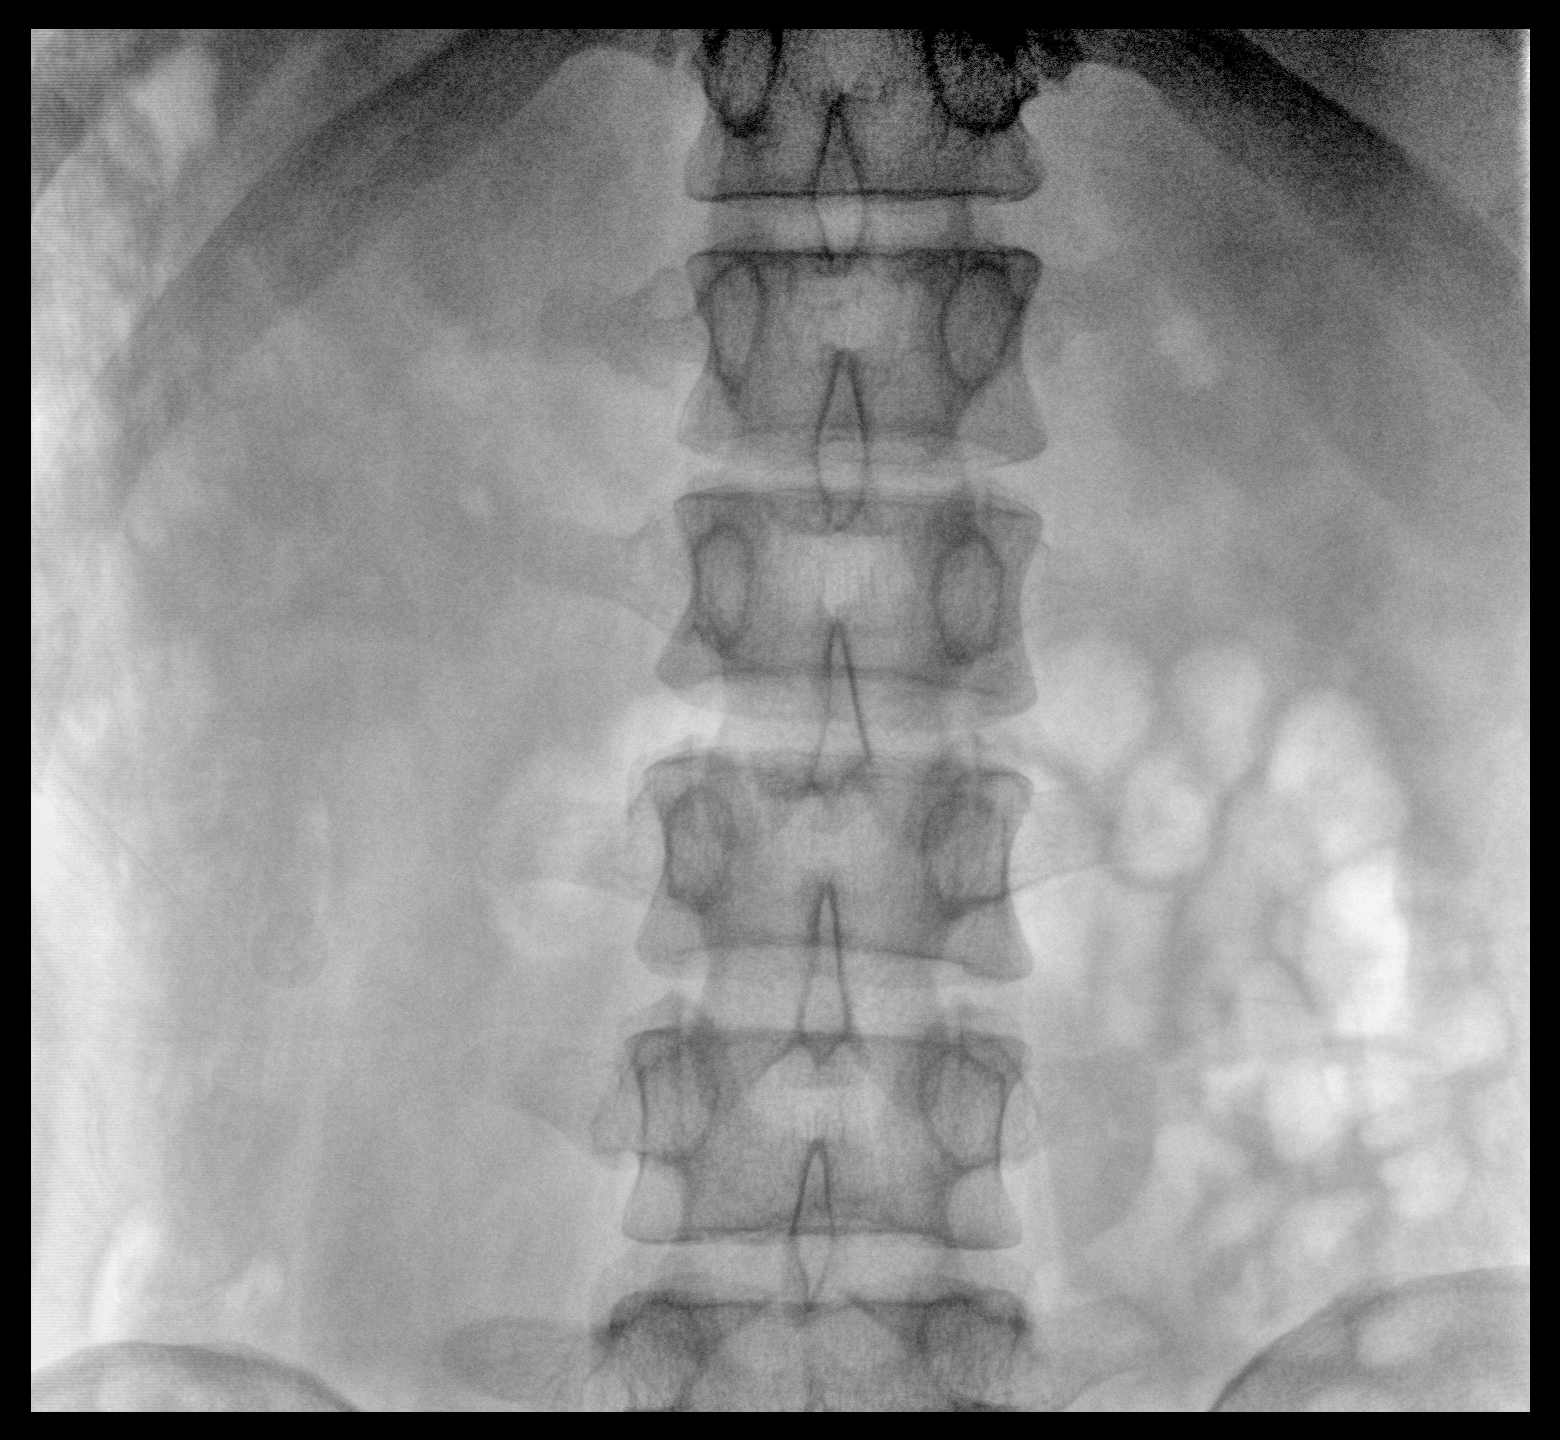

配備了兩種平板尺寸,大尺寸動(dòng)態(tài)平板探測(cè)器成像面積較傳統(tǒng)平板探測(cè)器提升了25%以上,在視野需求大的手術(shù)中,便于醫(yī)生更好定位病灶點(diǎn),規(guī)劃手術(shù)方案,減少因視野范圍不足而多次透視、點(diǎn)片造成的不便。

Clinical picture

臨床圖片